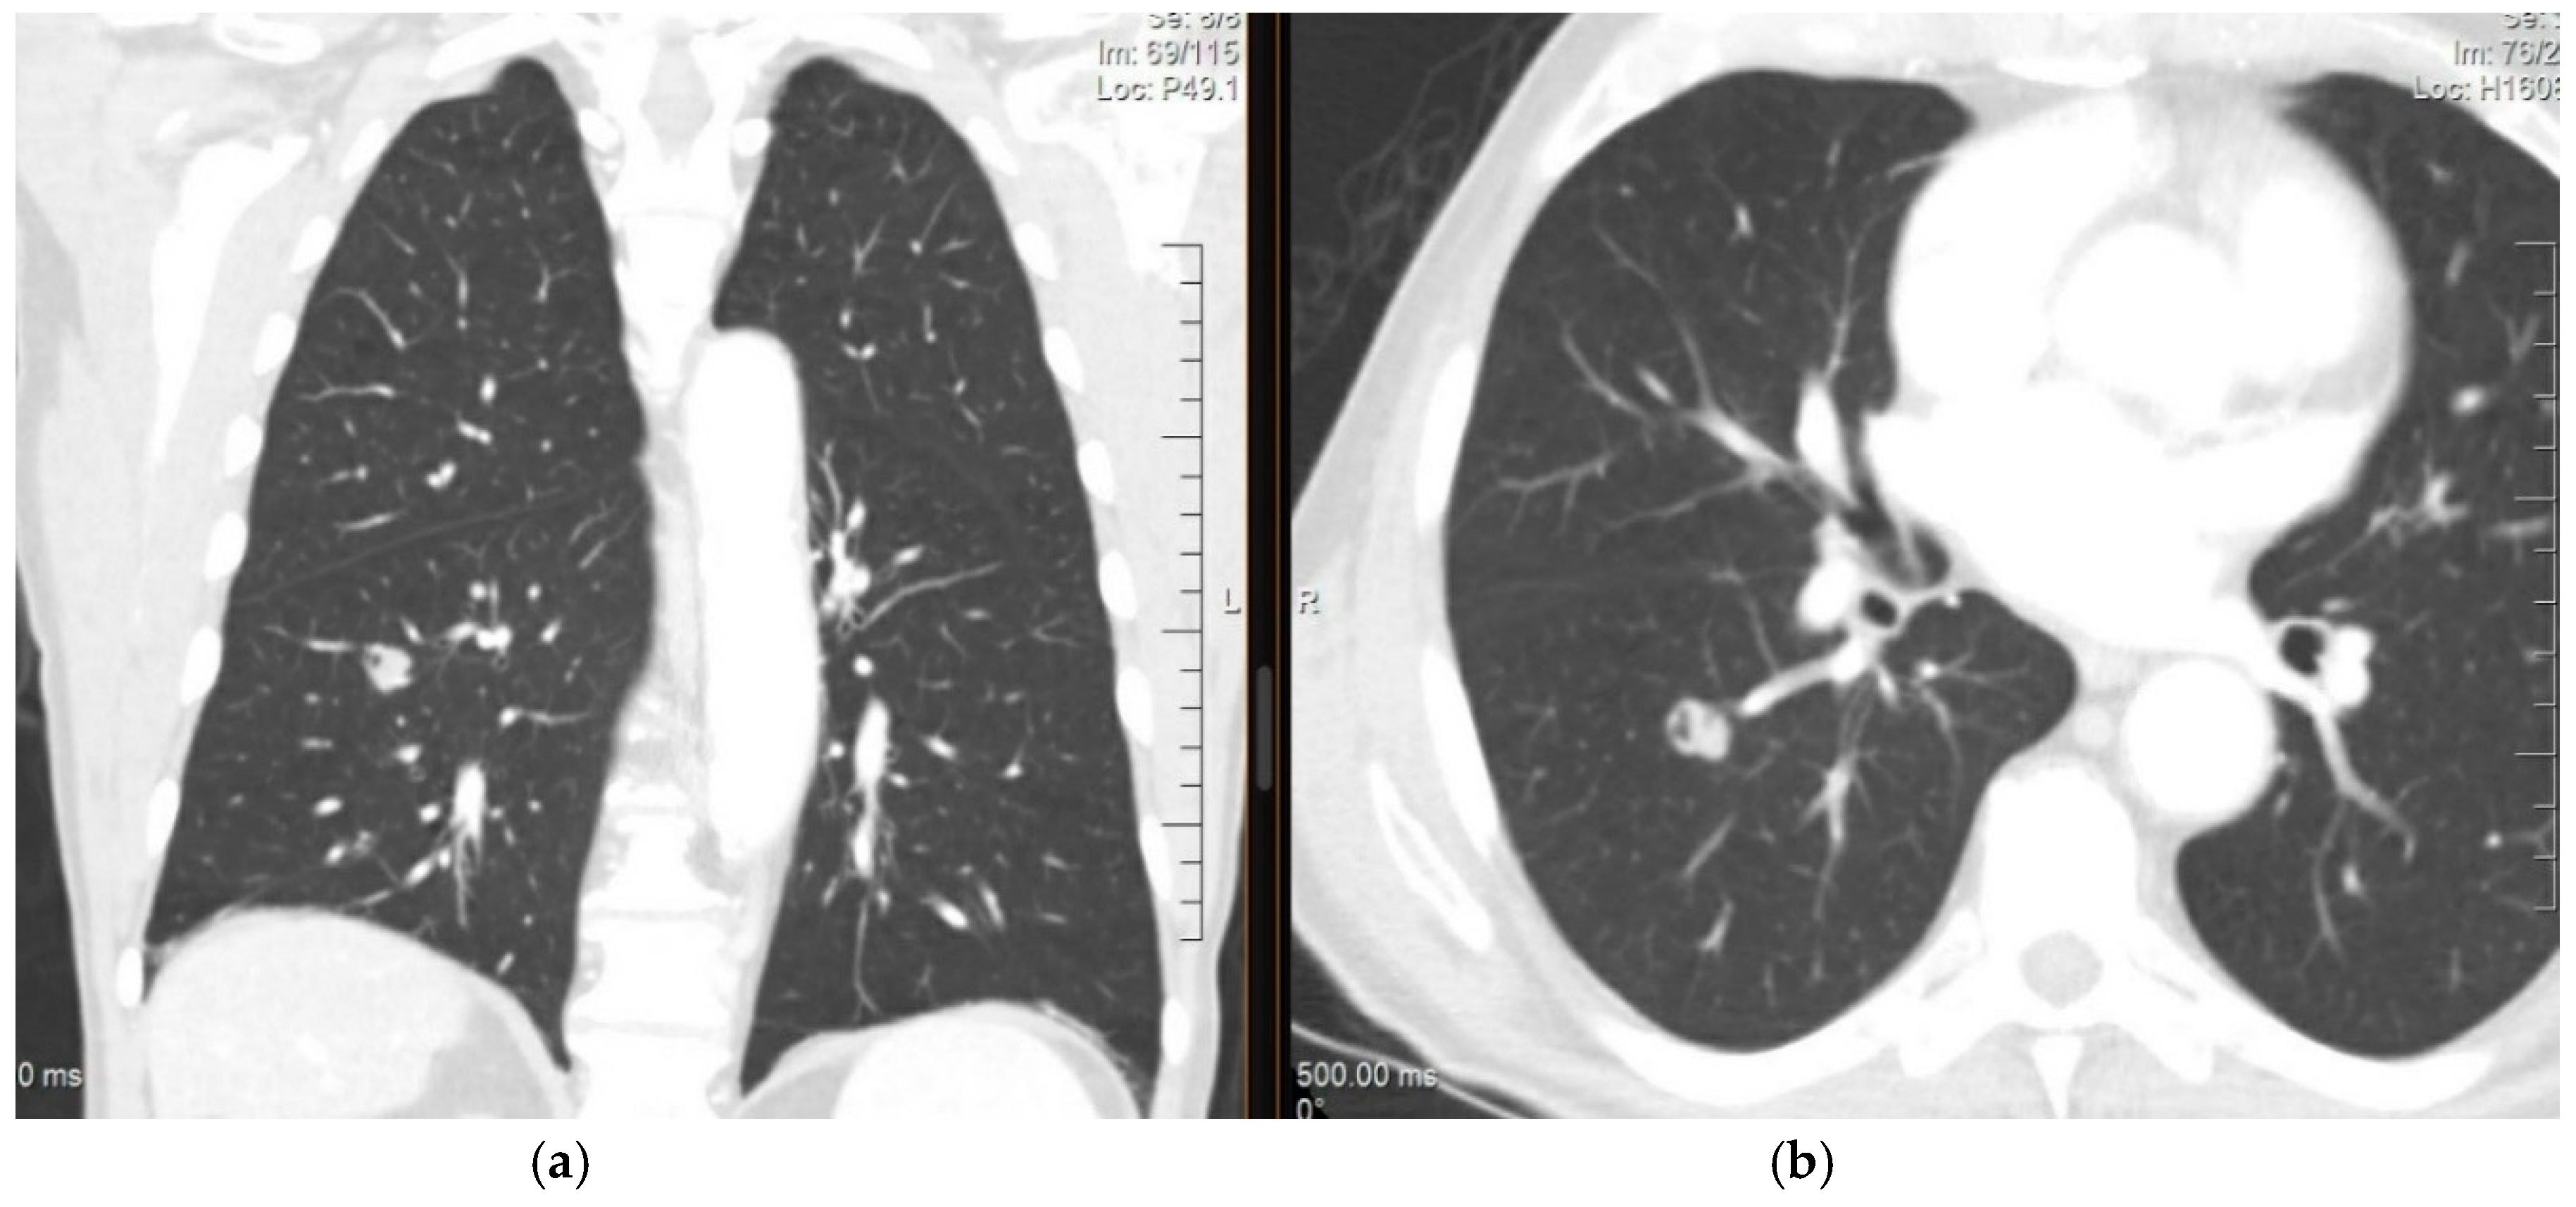

Chest computed tomography (CT) with slices of 1–1.25 mm is the preferred approach for assessing lungs to evaluate and determine the size of the lesion [27]. The characteristics of a metastatic lesion are widely variable. A new nodule > 10 mm has a 15% chance of malignancy, as shown in Figure 1. However, regardless of its size, an extrathoracic primary with a new lung lesion is highly suggestive of metastases. Malignant lesions commonly occur with spiculated and irregular margins. However, metastases should not be ruled out if the lesions are rounded and smooth [33].

Figure 1.

CT of the chest (a) coronal view and (b) axial view showing a nodule in the right lower lobe measuring 1.5 cm, lobulated and cavitated. The lesion was biopsied and revealed an adenocarcinoma with cytomorphology and an immunoprofile that was consistent with a colorectal primary.